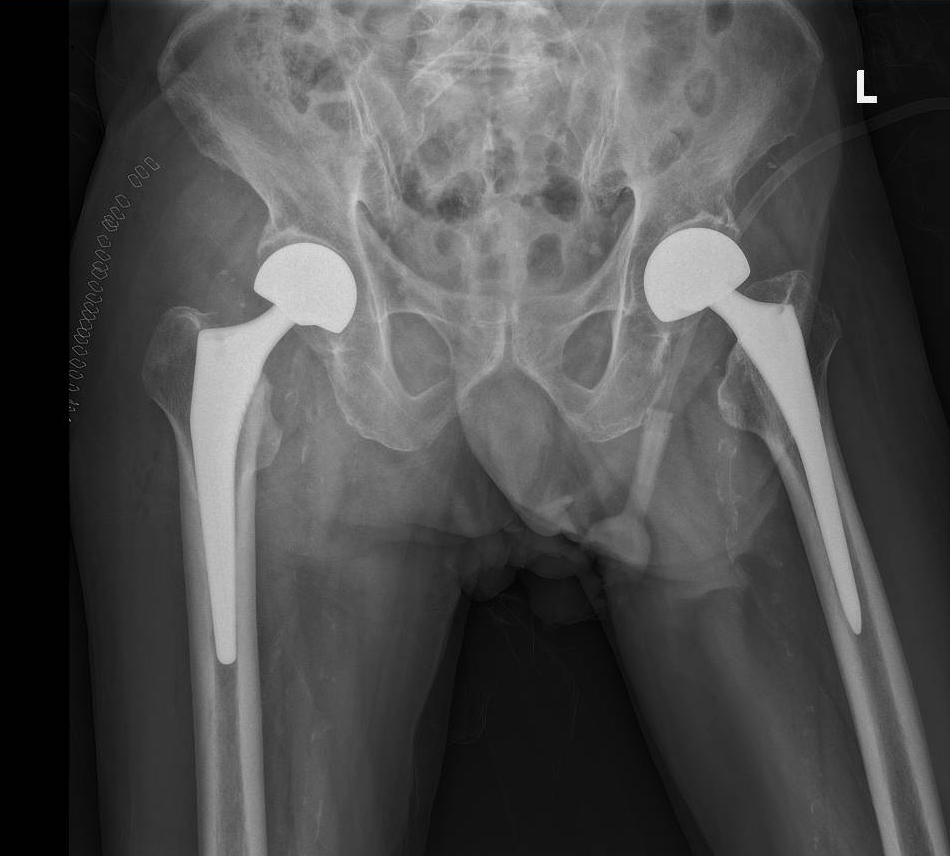

△冯爷爷术后X光片。

经查,冯爷爷确诊为右侧股骨颈骨折。更棘手的是,他既往有高血压、冠心病、肾功能不全等基础病史,且11年前曾因左侧股骨颈骨折在我院接受人工股骨头置换手术,此次属于右侧股骨颈骨折,手术难度和风险大幅增加。“11年前你们把我从鬼门关拉了回来,这次我还信你们!” 冯爷爷的信任,让四肢关节骨科团队备受鼓舞。科室负责人主任医师陈元庄及关节外科亚专科主任医师邬黎平牵头,组织麻醉科、心血管内科、肾内科、康复科等开展四级手术多学科讨论。

专家们反复评估冯爷爷的身体状况,精准制定了生物型人工股骨头置换术计划,同时针对其基础疾病制定了严密的围手术期管理方案,最大程度降低手术风险。

手术由四肢关节骨科主任医师莫华贵主刀,过程十分顺利。术后,在康复治疗师的专业指导和护理团队的精心照料下,冯爷爷恢复迅速,术后第3天便能借助助行器下地活动。“没想到这么大年纪还能再站起来,感谢医院给了我第二次生命!”冯爷爷及其家属感动不已,特意送来表扬信,向全体医护人员表达谢意!